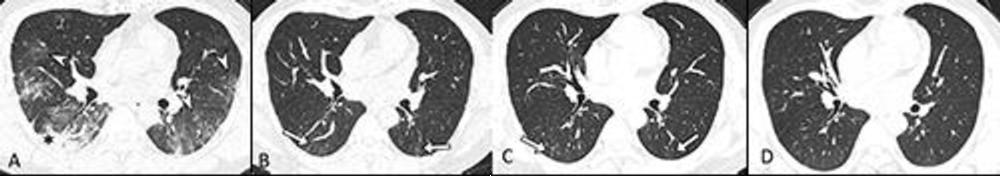

Figure 3. Serial transverse CT scans in a 67-year-old man with moderate COVID-19. (A) CT scan obtained on day 10 after onset of symptoms showed bilateral mixed pattern of ground-glass opacities and consolidation (*) in both lower and upper lobes. (B, C, D) Images obtained at 6-month, 12-month and 2-year follow up, respectively, showed persisting subpleural, bilateral linear, and curvilinear bands (white arrows) in both the lower and upper lobe. This patient did not report residual respiratory symptoms and had normal diffusing capacity of the lung for carbon monoxide (85%) at 2-year follow up.

High-res (TIF) version